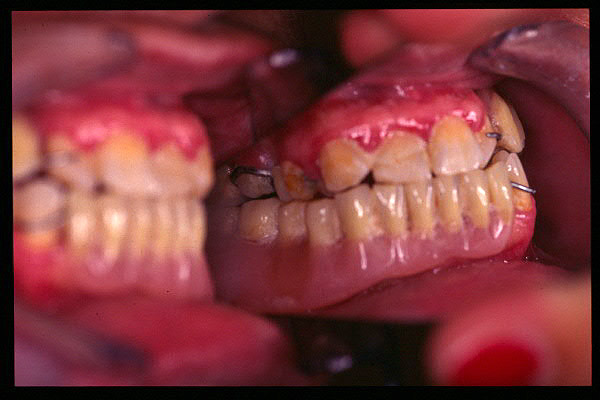

CM Enfermedad periodontal avanzada